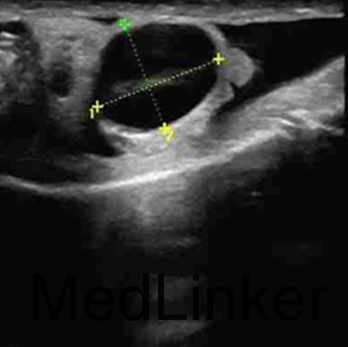

患者,男,27岁。 主诉:婚后9个月未育。 现病史:患者结婚9个月,正常房事,未曾行避孕措施,一直未育。2015-8-10于我院行精液常规未见精子。2015-8-11我院阴囊彩超示双侧附睾头囊肿,左右大小分别约为1.4*1.1cm,1.4*1.2cm。经直肠前列腺彩超示:前列腺呈炎性改变,右侧精囊正常,左侧精囊囊肿,大小约为3.2*2.2cm。性激素全套未见异常。2015-8-14复查精液常规仍未见精子,抑制素B定量为207.33pg/ml。2015-9-24精浆生化示:前列腺存在疾患,该病人属于梗阻性无精症,精囊缺如。门诊以射精管梗阻收入我科。 既往史:幼时曾有腮腺炎。